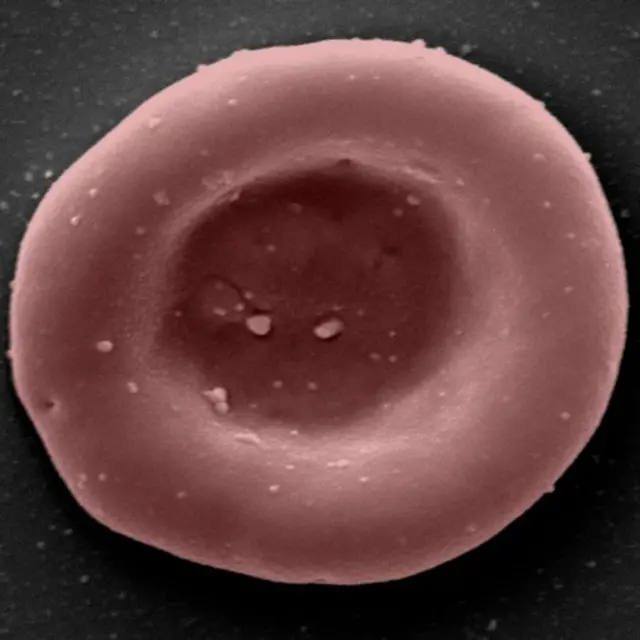

በዓለም የመጀመሪያ የሆነው ሰው ሰራሽ ደም በሰዎች ላይ መሞከር ተጀመረ

በቤተ ሙከራ ውስጥ የዳበረ ሰው ሰራሽ ደም ለመጀመሪያ ጊዜ በሚደረግ ክሊኒካዊ ሙከራ ለሰዎች መሰጠቱን የዩናይትድ ኪንግደም (ዩኬ) ተመራማሪዎች አስታወቁ።

ሰው ሰራሹን ደም ለማዳበር የብሪስቶል፣ የኬምብሪጅ፣ የለንደን እና የዩኬ ብሔራዊ የጤና አግልግሎት የምርምር አባላት እየተሳተፉ ነው። የፕሮጀክቱ ትኩረት ከሳንባ ወደ ቀሪው የሰውነት ክፍል ኦክስጂን በሚወስደው ቀይ የደም ህዋስ ላይ ነው።